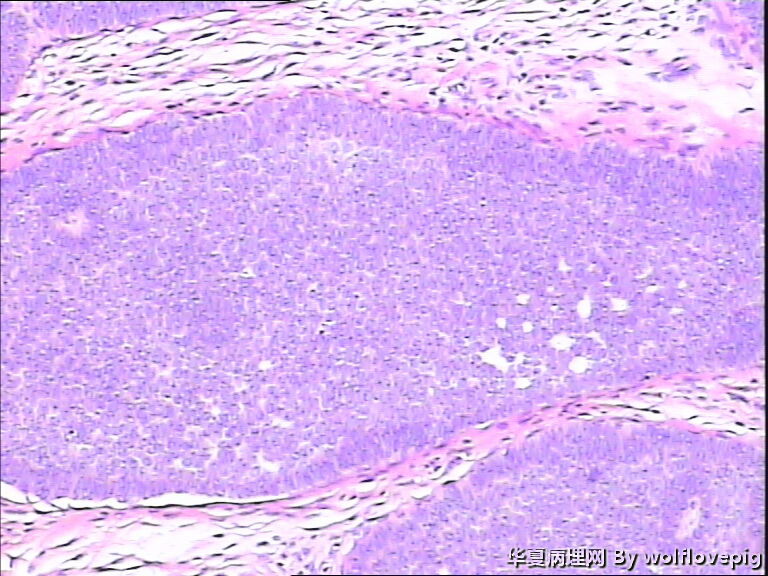

女,58y,右面部包块10年。灰白不整形带皮组织一块:2.3cm*1.5cm*0.3cm,切面有一灰白区域,质软,边界欠清。

图1

诊断考虑毛母细胞瘤,或毛发上皮瘤。

没有基底样物质,没有收缩裂隙,细胞异型不大,无明确核分裂像,考虑:附属器肿瘤,有点像汗腺来源的,如真皮导管瘤或螺旋瘤。请老师指点。

栅栏状外周结构,疏松的间质,基底细胞癌

与表皮无关,表皮无破溃,无收缩间隙-------不支持BCC  有角囊肿 促纤维增生-----支持毛发上皮瘤